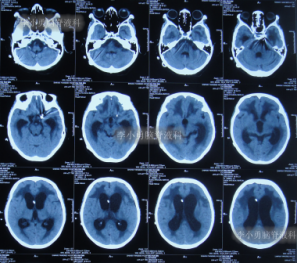

在李小勇主任的引领和培养下,一支技术过硬、敢于担当的医疗团队迅速成长。王光主任作为团队的核心骨干,深得李小勇主任技术精髓,在脑脊液引流、感染控制和围手术期管理方面经验丰富。他介绍,此次救治的71岁女性患者,情况就非常典型且危重。该患者因脑出血、动脉瘤术后继发脑积水,在外院接受了脑室腹腔分流术后,不仅症状未缓解,反而迅速恶化,出现持续昏迷、高热,复查发现脑积水进行性加重,生命垂危。经病友推荐,家属带着最后一线希望,于2021年9月将患者送至北京医大中西医结合医院脑脊液科。“患者来时意识不清,肺部有严重感染,右侧肢体偏瘫,脑积水的‘闸门’——分流管,很可能已经失效甚至成为感染源。”王光主任回忆道。面对这个“烂摊子”,科室迅速启动疑难病例讨论。在李小勇主任的总体指导下,以王光主任为主力的治疗组,为患者制定了周密的“三步走”方案。

入院第二天,李小勇主任团队就为患者实施了手术,拔除了那根可能已被细菌“占据”的旧分流管,清除了感染源,并重新建立了精准、可控的脑室外引流通道。这根新的“生命管道”如同为肿胀的大脑打开了一扇“减压窗”,颅内高压迅速得到缓解。

引流是基础,但战胜感染、改善患者全身状况才是康复的关键。在持续引流的同时,团队根据药敏结果使用敏感抗生素,并辅以营养神经、维持水电解质平衡、强化肺部分泌物引流等综合支持治疗。在医护人员的精心照料下,患者的体温逐渐恢复正常,意识从昏迷转为清醒,肺部感染也被有效控制。经过长达76天的精心准备,患者脑室缩小,颅内压力稳定,全身感染征象完全消失。此时,植入新分流管的最佳时机已然成熟。李小勇主任团队为患者成功实施了新的脑室腹腔分流术。这一次,分流系统在清洁、稳定的环境中开始正常工作。